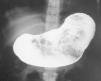

El hemograma y el estudio de hierro mostraron una anemia microcítica hipocroma (hemoglobina, 9,5 g/dl; hematócrito, 31,7 %; volumen corpuscular medio (VCM), 57,3 %; hemoglobina corpuscular media (HCM), 17,1 pg; MCHC, 29,9 g/dl, con 61 % de microcitos; sideremia, 12 μg/dl; transferrina, 375 mg/dl; ferritina menor de 1 ng/ml, índice de saturación de transferrina, 2 %. El resto del hemograma y de la bioquímica hemática incluyendo proteinograma, vitamina B12, hormonas tiroideas, ácido fólico, plomo, cinc y magnesio fueron normales. La radiografía simple de abdomen puso de manifiesto una marcada distensión abdominal, con un estómago ocupado por una imagen de alta densidad rodeada de un halo de gas. En el tránsito esofagogástrico (fig. 1) se observó una importante masa en el interior del estómago que ocupaba casi su totalidad. Ante la presencia de pica, anemia ferropénica y distensión abdominal se determinaron los anticuerpos antiendomisio y antitransglutaminasa IgA, que fueron positivos con títulos de 1/40 y más de 500 U/ml, respectivamente. Se realizó un estudio familiar de celiaquía a los padres que fue negativo. El diagnóstico definitivo de enfermedad celíaca se confirmó mediante una biopsia de mucosa de yeyuno proximal que demostró una atrofia vellositaria total (grado V de la clasificación de Metayer).

Figura 1. Tránsito esofagogástrico: cámara gástrica ocupada por una masa que dificulta su vaciado.